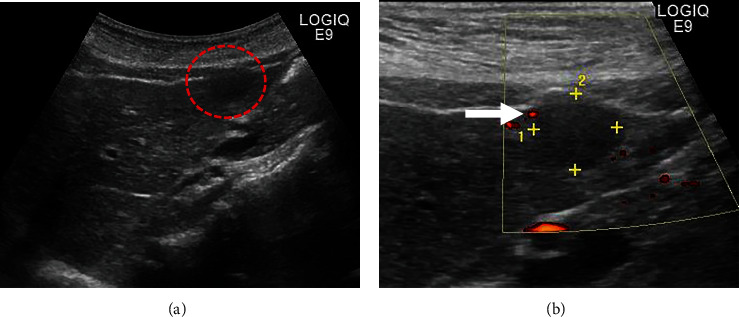

反应性淋巴细胞增生(RLH)是一种良性疾病,很少发生在肝脏。有报告称,反应性免疫现象与该病的发生有关,但真正的发病机制尚不清楚。目前还没有与炎症性肠病相关的病例报道。我们报告了一例溃疡性结肠炎(UC)患者的肝脏 RLH 病例。一名 55 岁的 UC 女性患者因腹痛前往门诊就诊,医生诊断为急性阑尾炎,并开了抗生素。影像学检查发现肝脏有肿块,但排除了阑尾炎的可能。疼痛好转后,她被转到我院接受进一步检查。超声波检查发现肝脏内有一个 12 毫米的低回声肿块。计算机断层扫描和磁共振成像没有发现典型的恶性病变。医生建议定期进行影像随访,但患者强烈要求手术治疗,因为他有家族恶性疾病史。患者接受了腹腔镜肝部分切除术。组织病理学检查结果显示,淋巴滤泡呈聚集性增生,并伴有生发中心。浸润的淋巴细胞未见新生物。最终诊断为肝脏 RLH。UC 是一种慢性炎症性肠病,可能与 RLH 有关,但目前尚无明确的解释。这是已知的首例 UC 患者肝脏 RLH 病例。但 RLH 与 UC 之间的关系仍不确定。有必要进行进一步的调查和病例积累。

Reactive lymphoid hyperplasia (RLH) is a benign disease, rarely occurring in the liver. Reactive immune phenomenon has been reported in association with its occurrence, but the true pathogenesis is unknown. No case was reported in association with inflammatory bowel disease. We report a case of RLH of the liver in a patient with ulcerative colitis (UC). A 55-year-old woman with UC went to the outpatient clinic with abdominal pain, and antibiotics were prescribed with diagnosis of acute appendicitis. Imaging study detected a mass in the liver but ruled out appendicitis. She was referred to our hospital for further examination after pain improving. A 12 mm hypoechoic mass was detected in the liver on ultrasonography. There were no typical malignant findings on computed tomography and magnetic resonance imaging. Regular image follow-up was recommended, but the patient strongly requested surgery because of family history of malignant disease. Laparoscopic partial hepatectomy was performed. Histopathological findings revealed a conglomerate hyperplasia of lymphoid follicles with germinal centers. Infiltrating lymphocytes were non-neoplastic. Final diagnosis was RLH of the liver. UC is chronic inflammatory bowel disease and may be related to RLH, but there is no clear explanation at this point. This is the first known reported case of RLH of the liver in a patient with UC. But the relationship between the RLH and UC remains uncertain. Further investigation and case accumulation are necessary.